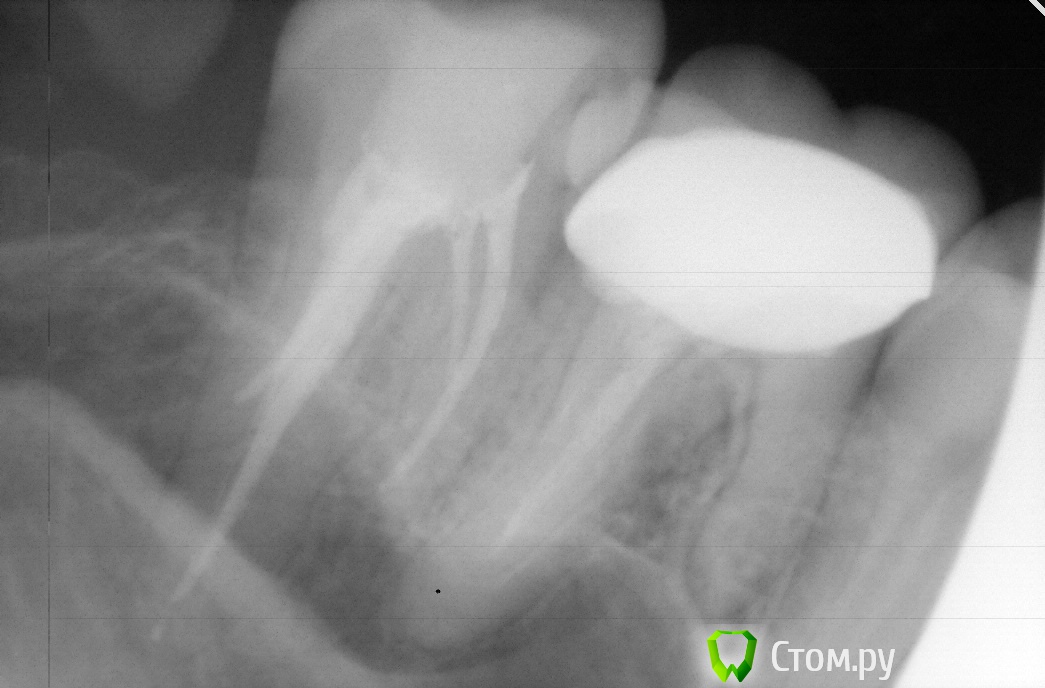

Денис481 Опубликовано 13 ноября, 2013 Поделиться Опубликовано 13 ноября, 2013 после курсов начали находится каналы)))фото с 4 мя потом с небным,небный не понравился,перелечил Ссылка на комментарий

Денис481 Опубликовано 13 ноября, 2013 Автор Поделиться Опубликовано 13 ноября, 2013 (изменено) к 1 есть недопак чуть,1,5 мм на втором дистально щеном,а вообще непонятная ситуация апкекс орет,пин кончик с кровью,а на снимке недопак,я небный переделал,а особо картина не поменялась,но при пульпите это не критично Изменено 13 ноября, 2013 пользователем Денис481 Ссылка на комментарий

АнтонТЛТ Опубликовано 13 ноября, 2013 Поделиться Опубликовано 13 ноября, 2013 к 1 есть недопак чуть,1,5 мм на втором дистально щеном,а вообще непонятная ситуация апкекс орет,пин кончик с кровью,а на снимке недопак,я небный переделал,а особо картина не поменялась,но при пульпите это не критичноТак может там перфа просто? Снимки с файлами есть? Ссылка на комментарий

Денис481 Опубликовано 13 ноября, 2013 Автор Поделиться Опубликовано 13 ноября, 2013 не там изначально апекс такую длину показал,а ренген нет,вот я и думал,в другой проекции все хорошо,на небном,а вот на щечном явно недолет Ссылка на комментарий